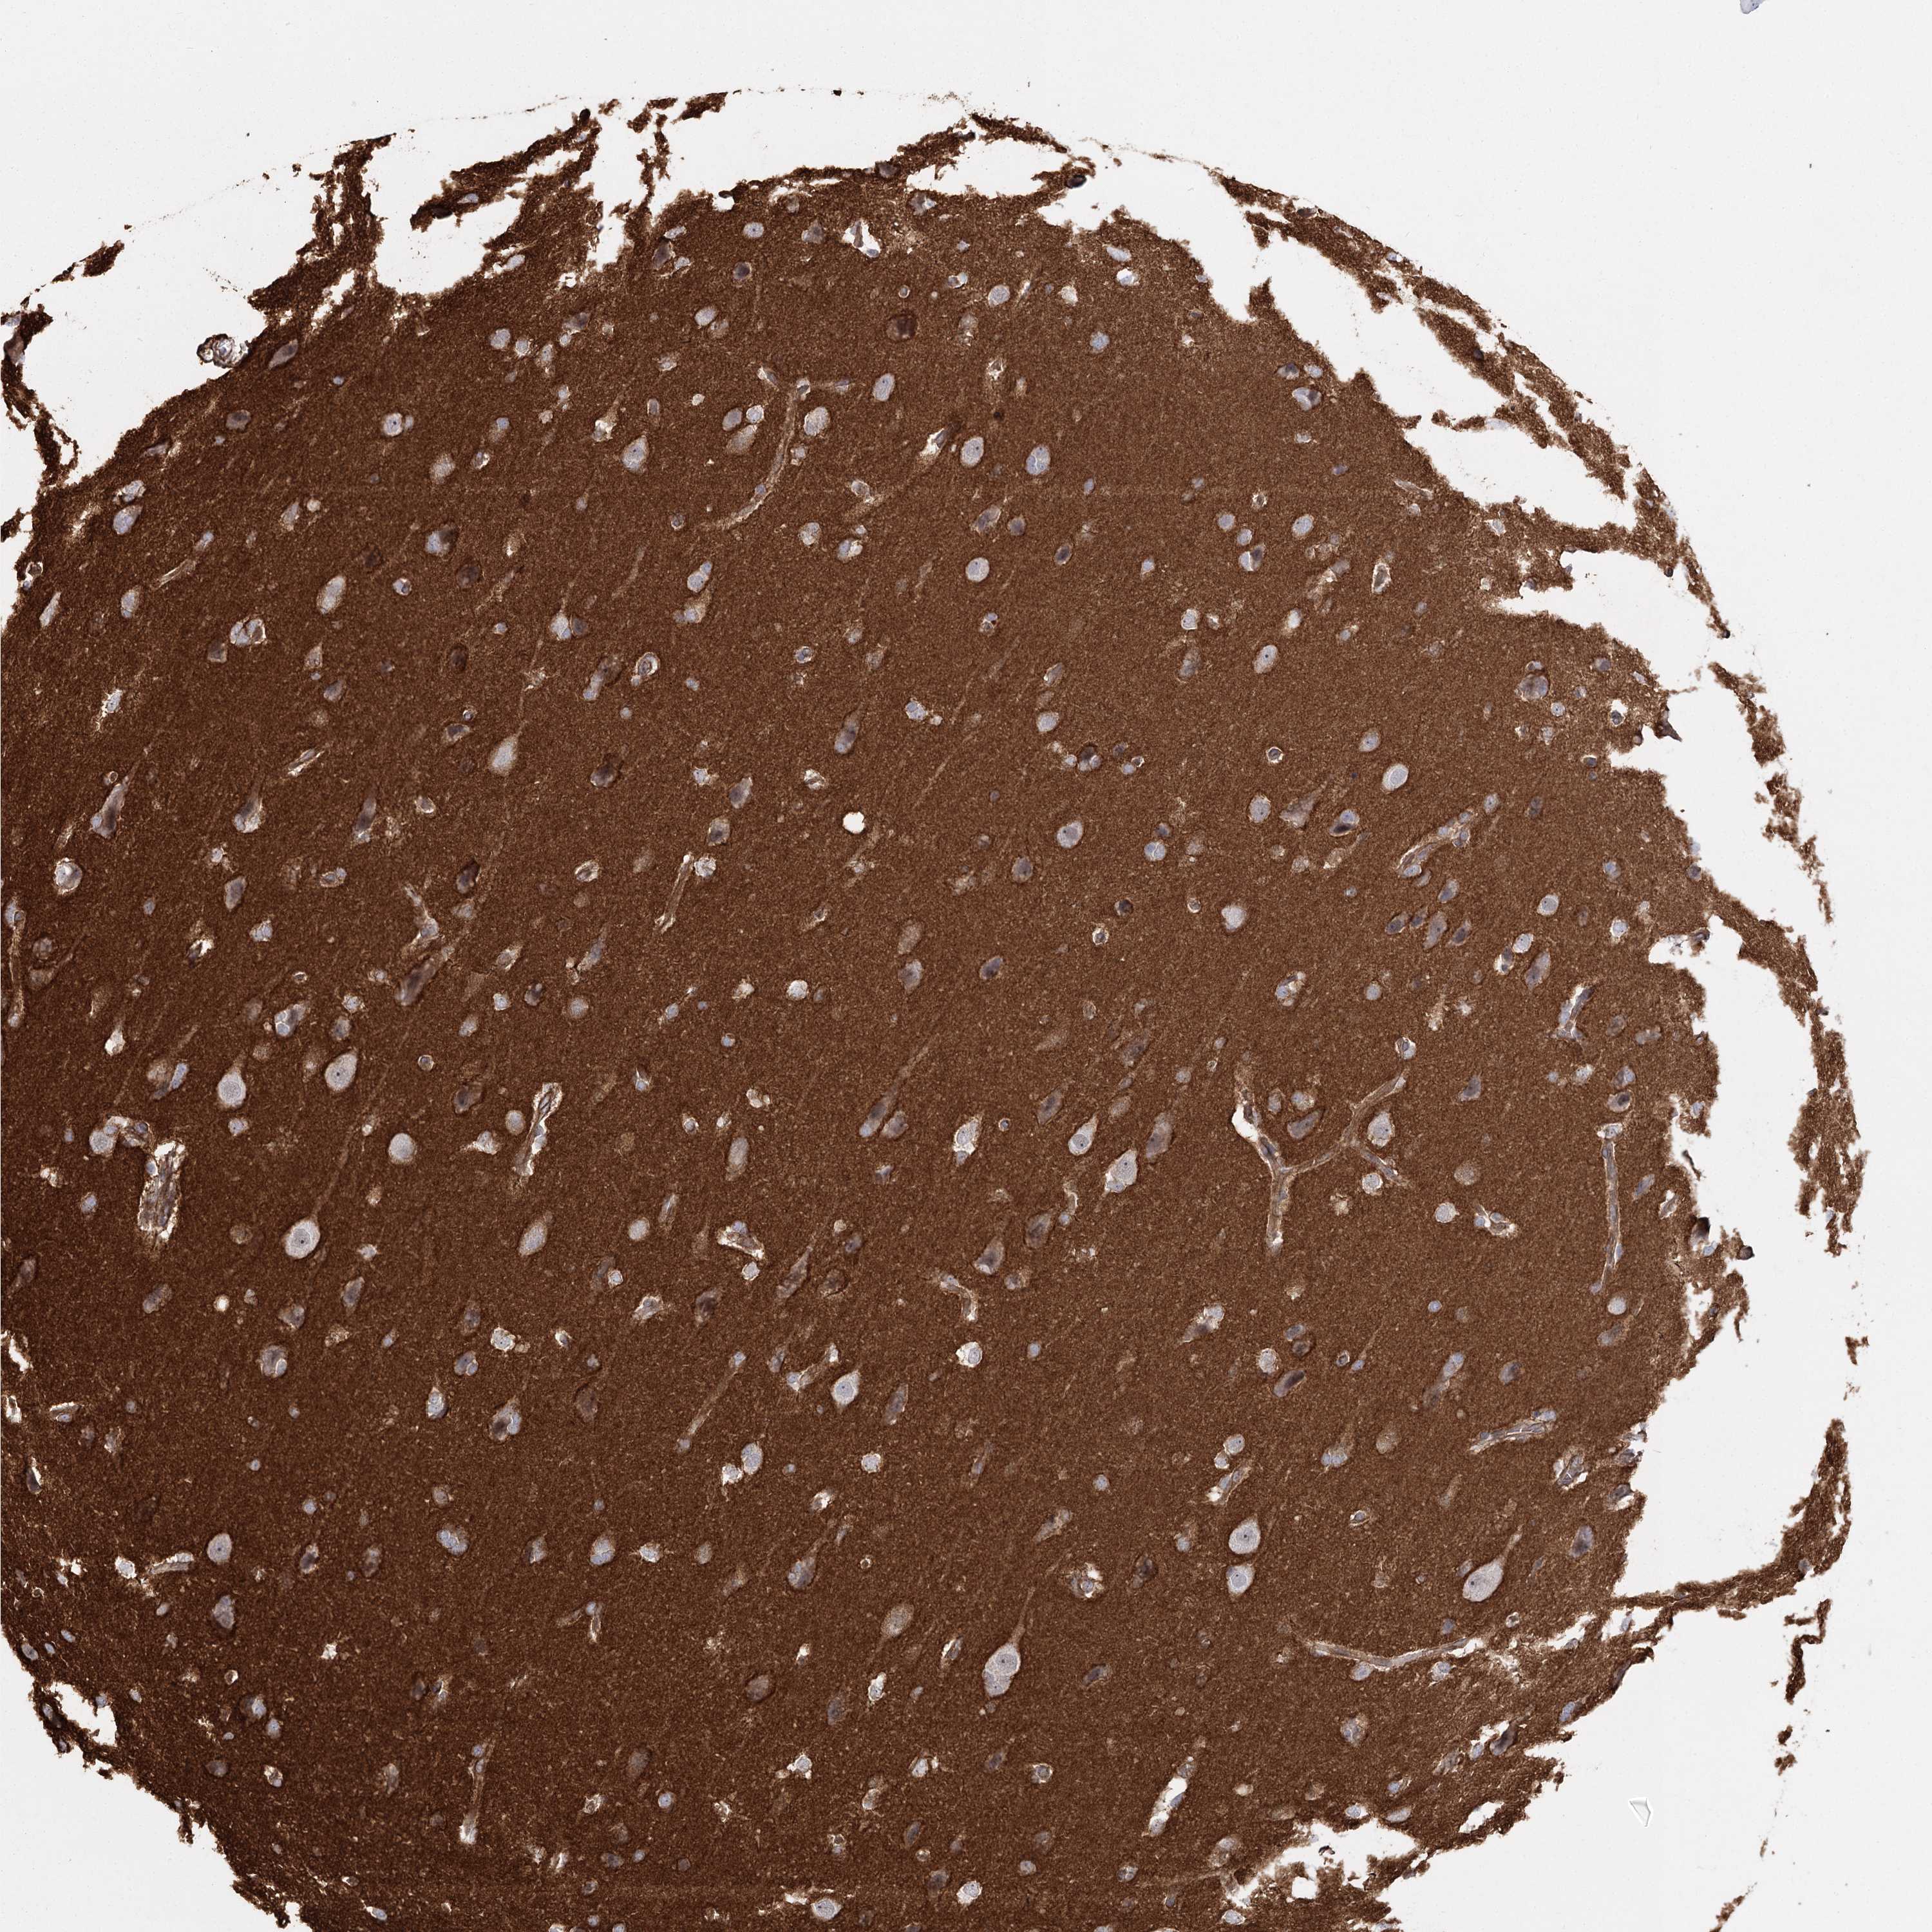

GLIOMA - Protein expressioni

A mouse-over function shows sample information and annotation data. Click on an image to view it in a full screen mode. Samples can be filtered based on level of antibody staining by selecting one or several of the following categories: high, medium, low and not detected. The assay and annotation is described here.

Note that samples used for immunohistochemistry by the Human Protein Atlas do not correspond to samples in the TCGA dataset.

Antibody stainingi

Antibody staining in the annotated cell types in the current human tissue is reported as not detected, low, medium, or high, based on conventional immunohistochemistry profiling in selected tissues. This score is based on the combination of the staining intensity and fraction of stained cells.

Each image is clickable and will lead to virtual microscopy that enables deeper exploration of all samples and also displays staining intensity scores, fraction scores and subcellular localization as well as patient and tissue information for each sample.

Antibody HPA036194

Staining

High

Medium

Low

Not detected

Intensity

Strong

Moderate

Weak

Negative

Quantity

>75%

75%-25%

<25%

None

Location

Nuclear

Cytoplasmic/membranous

Cytoplasmic/membranous,nuclear

Glioma, malignant, Low grade